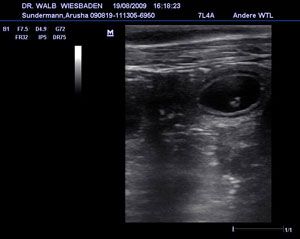

Der Ultraschall hat es ans Licht gebracht: Arusha wird Mama!